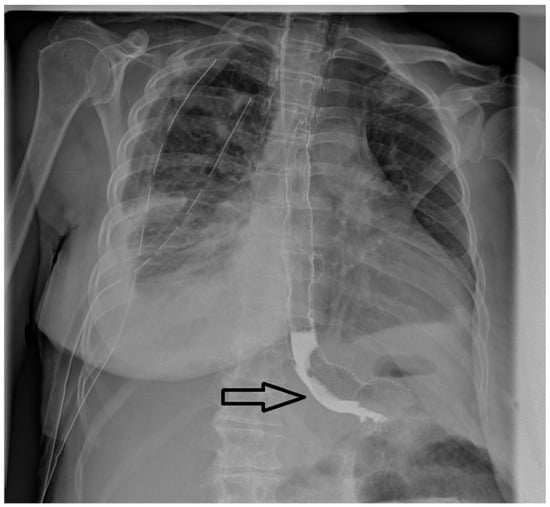

Upper gastrointestinal endoscopies were conducted under general anesthesia, with orotracheal intubation and X-ray guidance (Figure 1).

Figure 1. Radiological appearance after deployment of the esophageal stent within an eso-jejunal anastomotic fistula after the surgical resection of a gastric neoplasm.